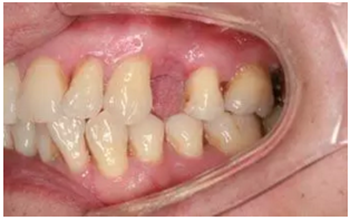

從圖1可以看出患者缺牙區(qū)的間隙充足,牙齦健康,頰側(cè)軟組織略有凹陷。

圖1 缺牙區(qū)的頰側(cè)和口內(nèi)照片